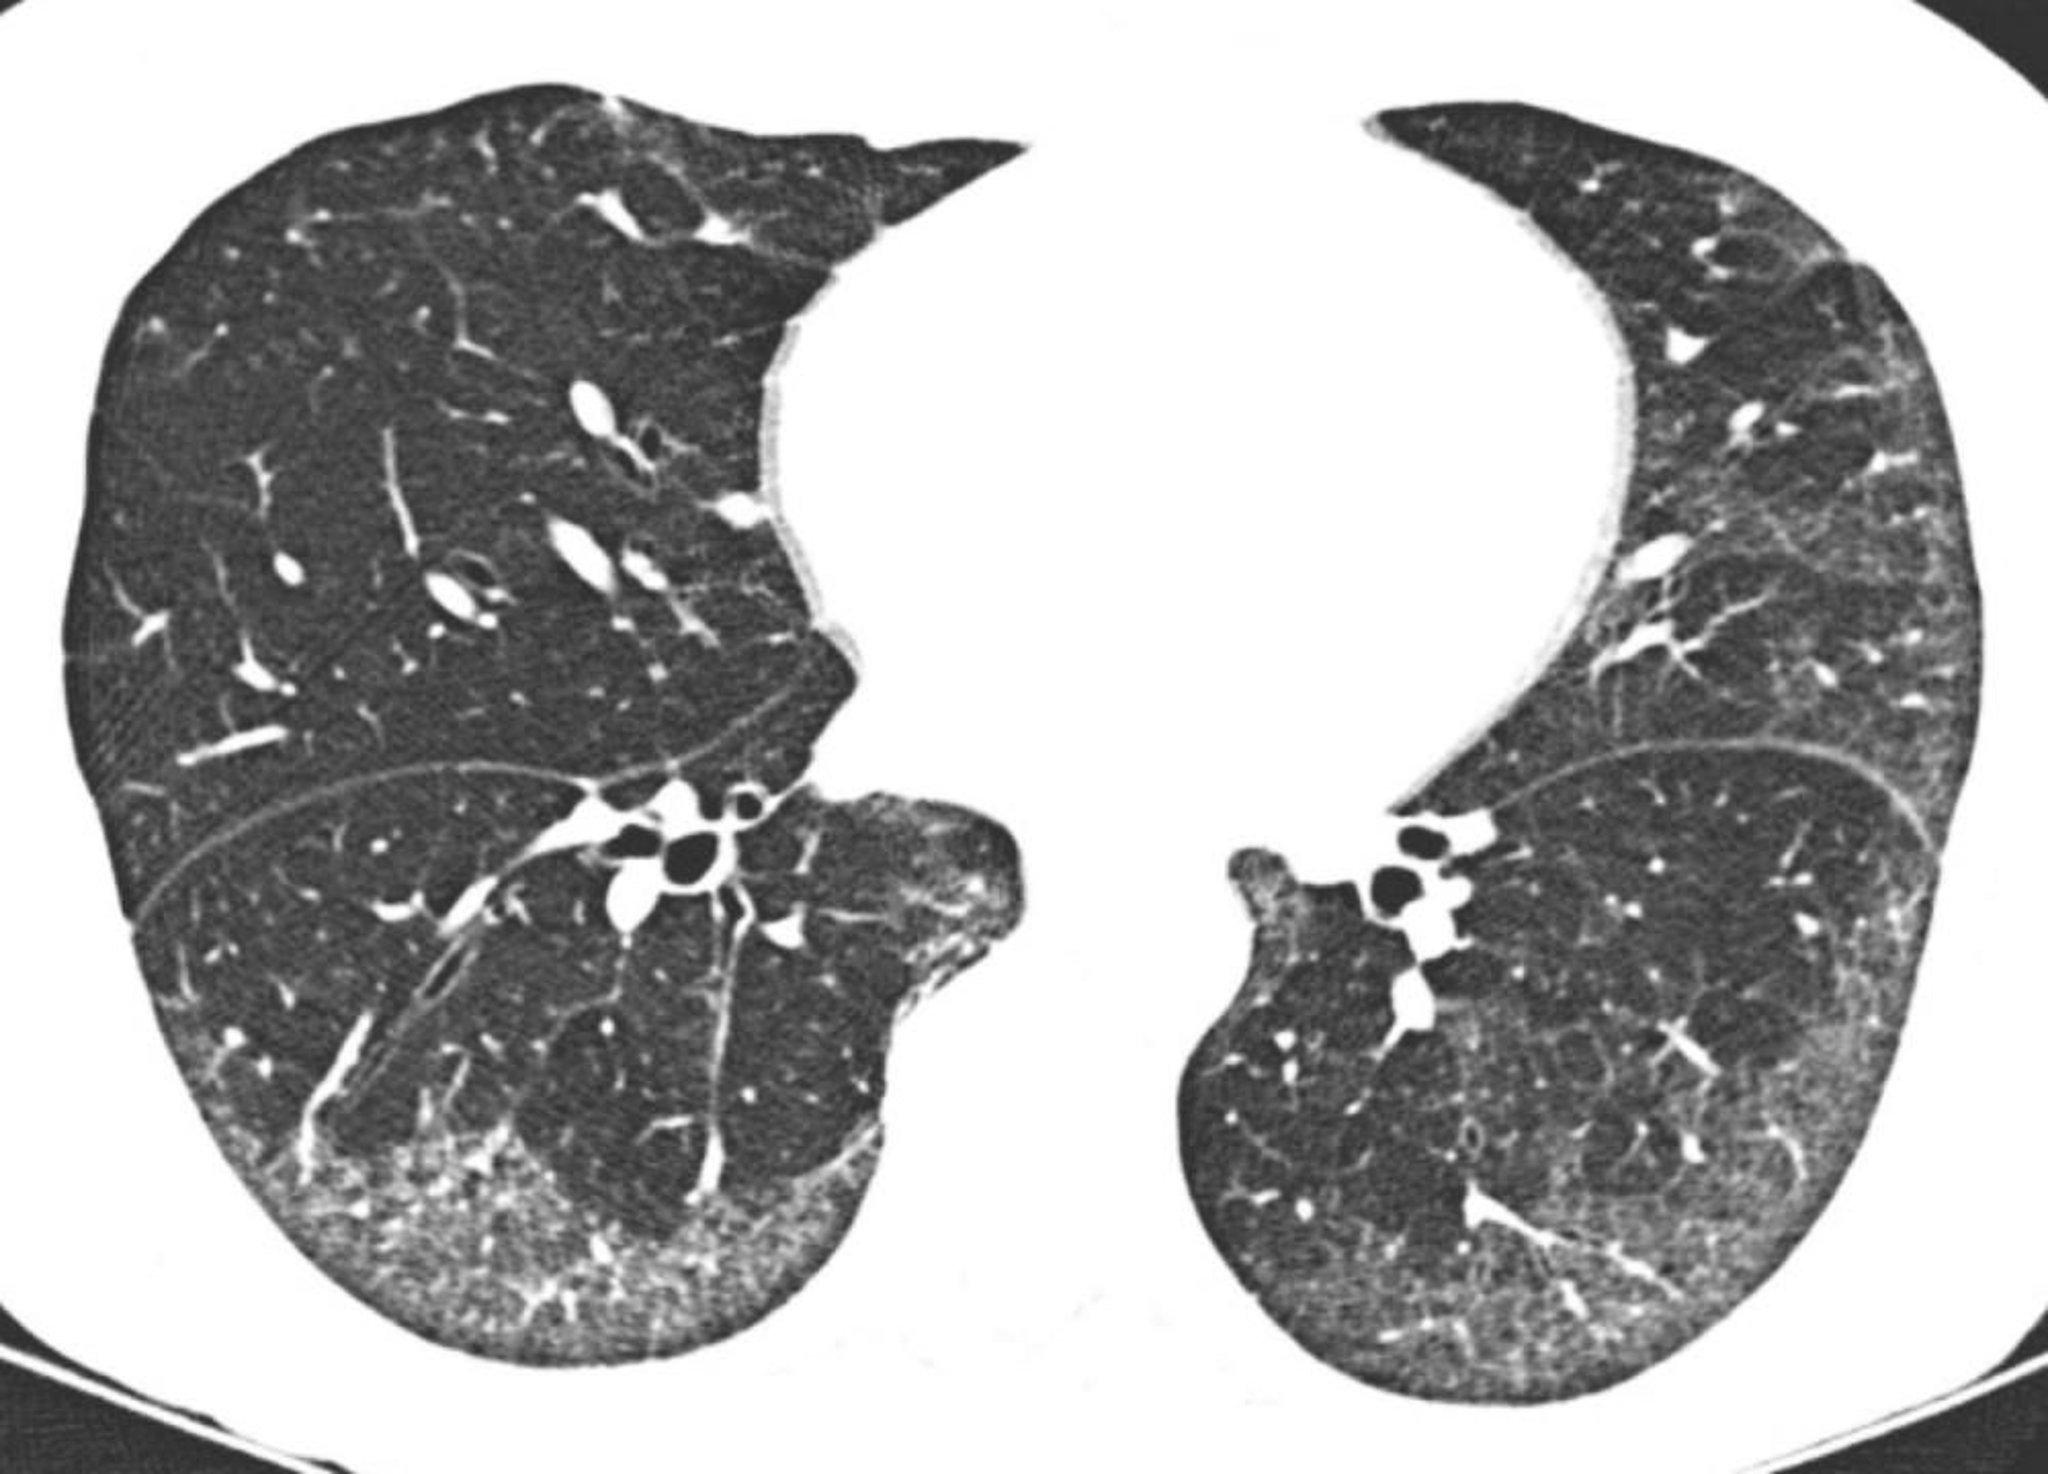

高分解能CTで,胸膜下および肺底部優位のすりガラス陰影がみられる。胸膜直下が比較的正常であるのは,非特異性間質性肺炎に典型的な所見である。

Image courtesy of Harold R.Collard, MD.